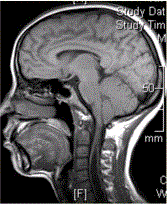

问题 患者女,40岁,手部麻木数年。MR显示如下图。 关于各型Chiari畸形的描述,错误的是

选项 A.Ⅰ型,常见,可伴有脑积水,脊髓空洞,环枕区畸形 B.Ⅱ型,最常见。小脑下蚓部、桥脑下部、延髓下移、Ⅳ脑室延长。伴有脊髓脊膜膨出,腰骶部多见(3/4) C.MR矢状位清晰显示小脑扁桃体,延髓位置及IV脑室形态、位置 D.MR可显示脑积水、脑膜膨出 E.不伴有大脑镰、天幕发育不良

答案 E